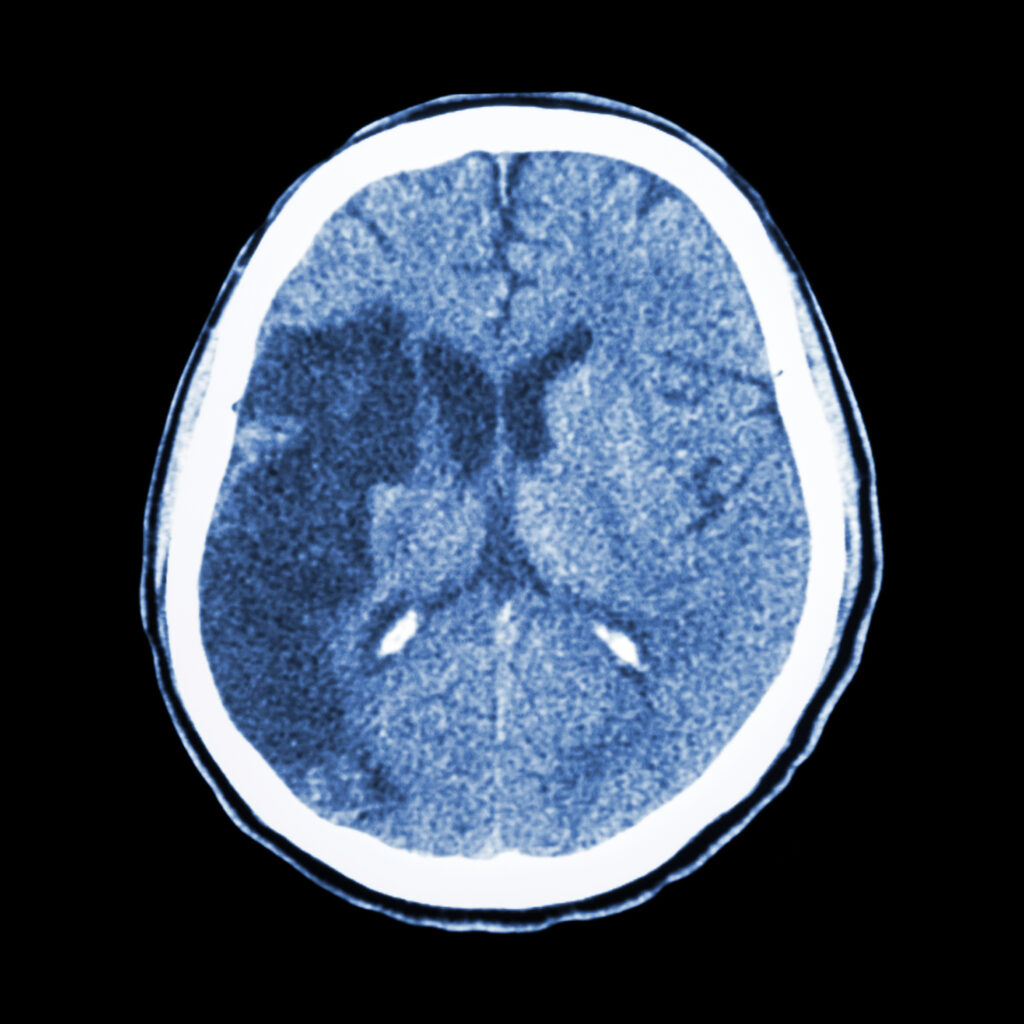

• Cérebro. Pode ocasionar confusão mental, convulsões ou mesmo um derrame.

Acometimento do sistema nervoso central: quando o Lúpus atinge o cérebro

O Lúpus também pode afetar o cérebro e o sistema nervoso central.

Esse é um dos sintomas de Lúpus mais delicados e preocupantes da doença, porque muitas vezes surge de forma inesperada e altera funções essenciais do dia a dia.

Os sintomas podem incluir:

• Cefaleias persistentes e intensas

• Perda de memória recente ou dificuldade de concentração

• Alterações de comportamento

• Ansiedade ou depressão de início súbito

• Sensação de “confusão mental”

• Convulsões

• Acidente Vascular Cerebral (AVC ou derrame) em pessoas jovens

Quando o Lúpus atinge o sistema nervoso, o impacto pode ser dramático.

Uma mulher jovem pode apresentar um AVC e subitamente perder a fala ou os movimentos de um lado do corpo.

Em outros casos, surgem crises convulsivas difíceis de controlar.

Há também situações em que o comportamento muda de maneira brusca, com agitação, agressividade, delírios ou quadros que se parecem muito com transtornos psiquiátricos.

A pessoa que antes era funcional passa a ter lapsos de memória, dificuldade de executar tarefas simples e alterações emocionais sem causa aparente.

Por isso, qualquer suspeita de acometimento neurológico no Lúpus exige avaliação rápida e acompanhamento especializado multidisciplinar.